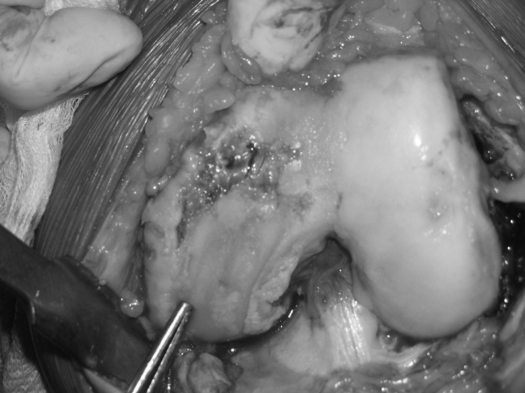

Hư hại hoàn toàn sụn khớp trong thoái hoá khớp là nguồn gốc cơn đau khớp gối khi đi và gây ra tiếng kêu lạo xạo khi cử động - Ảnh: TS. Tăng Hà Nam Anh